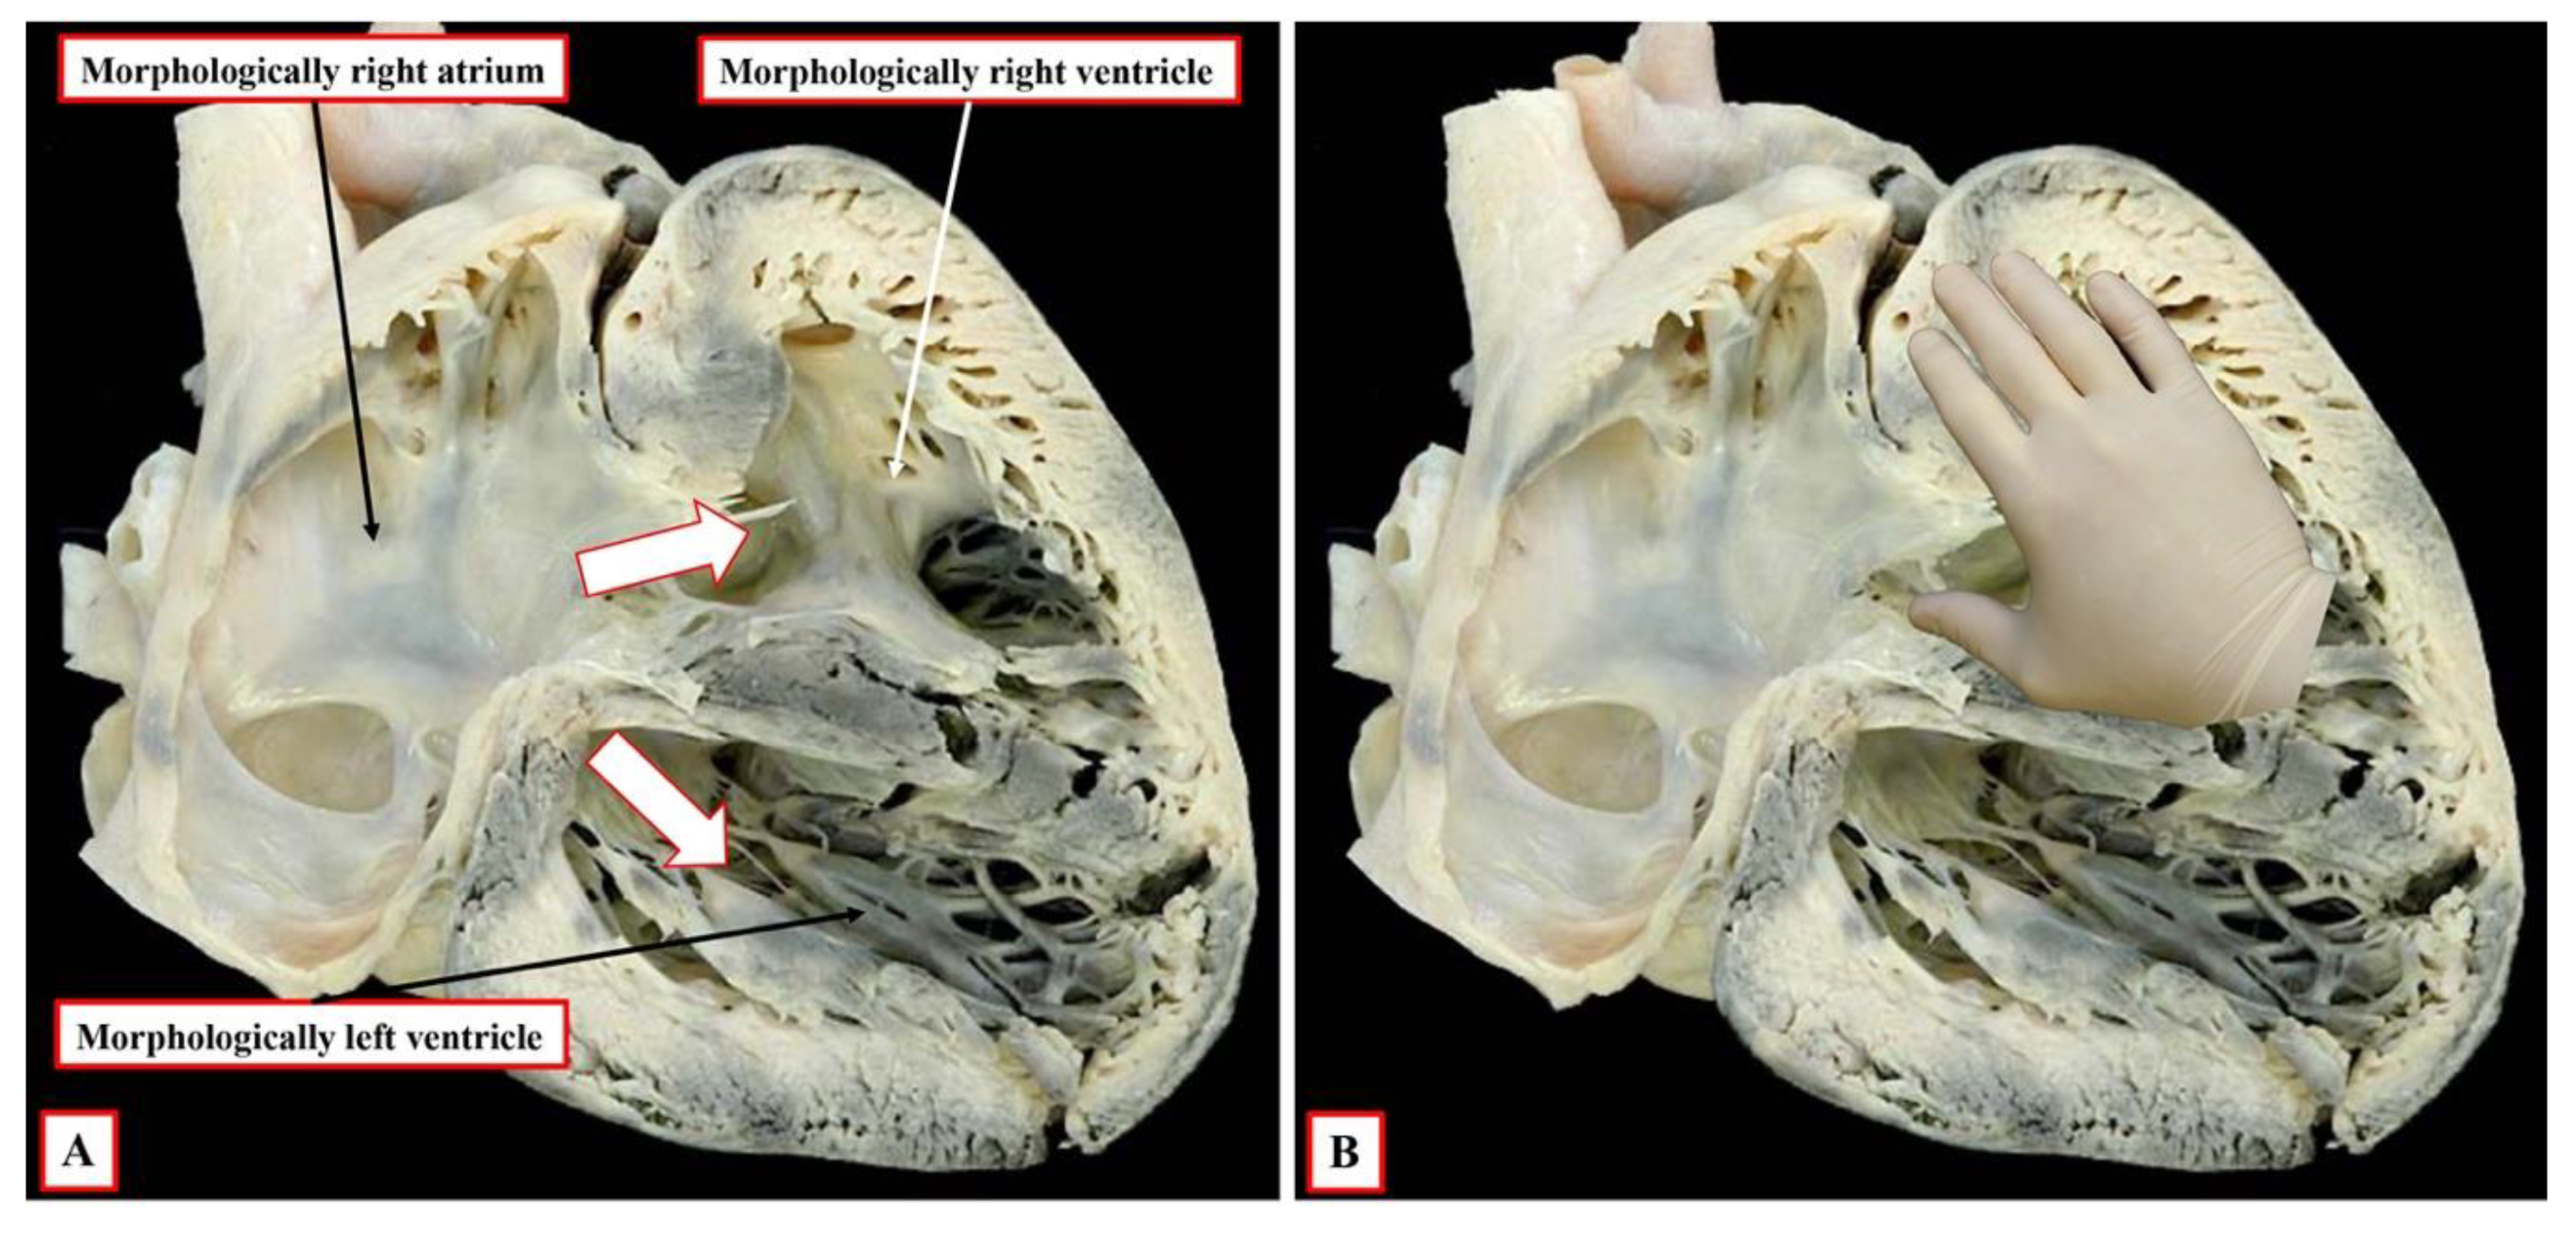

It is the next stage of development that sets the scene for the establishment of ventricular topology. Simply by expansion of the atrioventricular canal, the right ventricle achieves its own inlet component. In the murine heart, this process occurs between embryonic days 10.5 and 11.5 (Compare

Figure 2 and

Figure 3). In the human heart, the period encompasses the fifth and sixth weeks of development subsequent to fertilisation. Once it has achieved its own inlet (

Figure 3A), even though it continues to support the entirety of the outflow tract, the right ventricle can be recognised to have achieved right-handed topology (

Figure 3B). It is the morphologically right ventricle, by convention, that is used as the arbiter of ventricular topology or chirality. The concept depends on the ability, figuratively speaking, to place the palmar surface of the hands on the septal surface of the right ventricle. The thumb is placed in the tricuspid valve, the wrist occupies the apical trabecular component, and the fingers extend into the ventricular outflow tract. In the normal heart, once the right ventricle has developed its own inlet (

Figure 3B), it is only the palm of the right hand that fits the septal surface of the morphologically right ventricle (

Figure 4A). In the setting of congenitally corrected transposition, in contrast, which is itself the consequence of the development of discordant atrioventricular connections, and when the atrial chambers are in their usual positions, it is only the palmar surface of the left hand that can be placed on the septal surface (

Figure 4B).

It follows, of course, that the left hand could be placed on the septal surface of the morphologically left ventricle in the setting of right-handed topology and the right hand when there is left-handed topology. Convention, nonetheless, has dictated that the right ventricle should be used as the landmark. It also follows that, should congenitally corrected transposition be found in the setting of mirror-imaged atrial arrangement, then the ventricular mass, almost without exception, shows right-handed topology. The caveat, however, is “almost without exception”. On very rare occasions, the ventricular topology is disharmonious with the fashion in which the cavities of the atrial chambers are joined to the ventricles. It is the feature of the flow pathways across the atrioventricular junctions, of course, which is used in the sequential segmental approach to define the segmental connections. Within the segmental approach, however, the so-called “alignments” must be inferred from the information provided within the segmental set. Thus, those with {S,D,*} are presumed to have concordance. This means that, in transposition {S,D,D}, the segmental notation indicates that the atrial and ventricular chambers are joined together in a morphologically appropriate fashion. In transposition {S,L,L}, the segmental notation would indicate that the atrial chambers are joined to morphologically inappropriate ventricles. This system, however, fails to account for disharmony between the morphology of the segments and the connections between them.